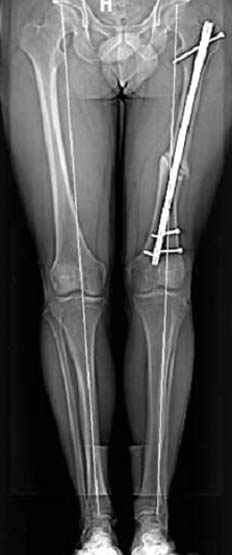

Несколько снимков из моей коллекции, чтобы разьяснить, почему мы до сих пор делаем различные варианты остеотомии.

На рисунке N1 предоперационный план лечения ложного сустава шейки бедра- линия ложного сустава, угол и направление введения импланта, клиновидная остеотомия в градусах и миллиметрах, второй снимок после коррекции, расчет, на сколько удлиняется конечность и размеры импланта;

N3 рисунок окончательный снимок, после операции моя рентгенограмма должен выглядеть примерно как эта картина. На N4 снимке клин перед удалением; N5 послеоперации 3 нед.; N6 окончательная рентгенограмма.

варус при проксимальном отделе 95 градусной пластиной.

Интересно бы посмотреть рентгенограмму таза (оба сустава) а также рентгенгорамму с захватом коленных суставов (по Dror Paley).

пластическая модель; и коррекция бедра аппаратом Илизарова.